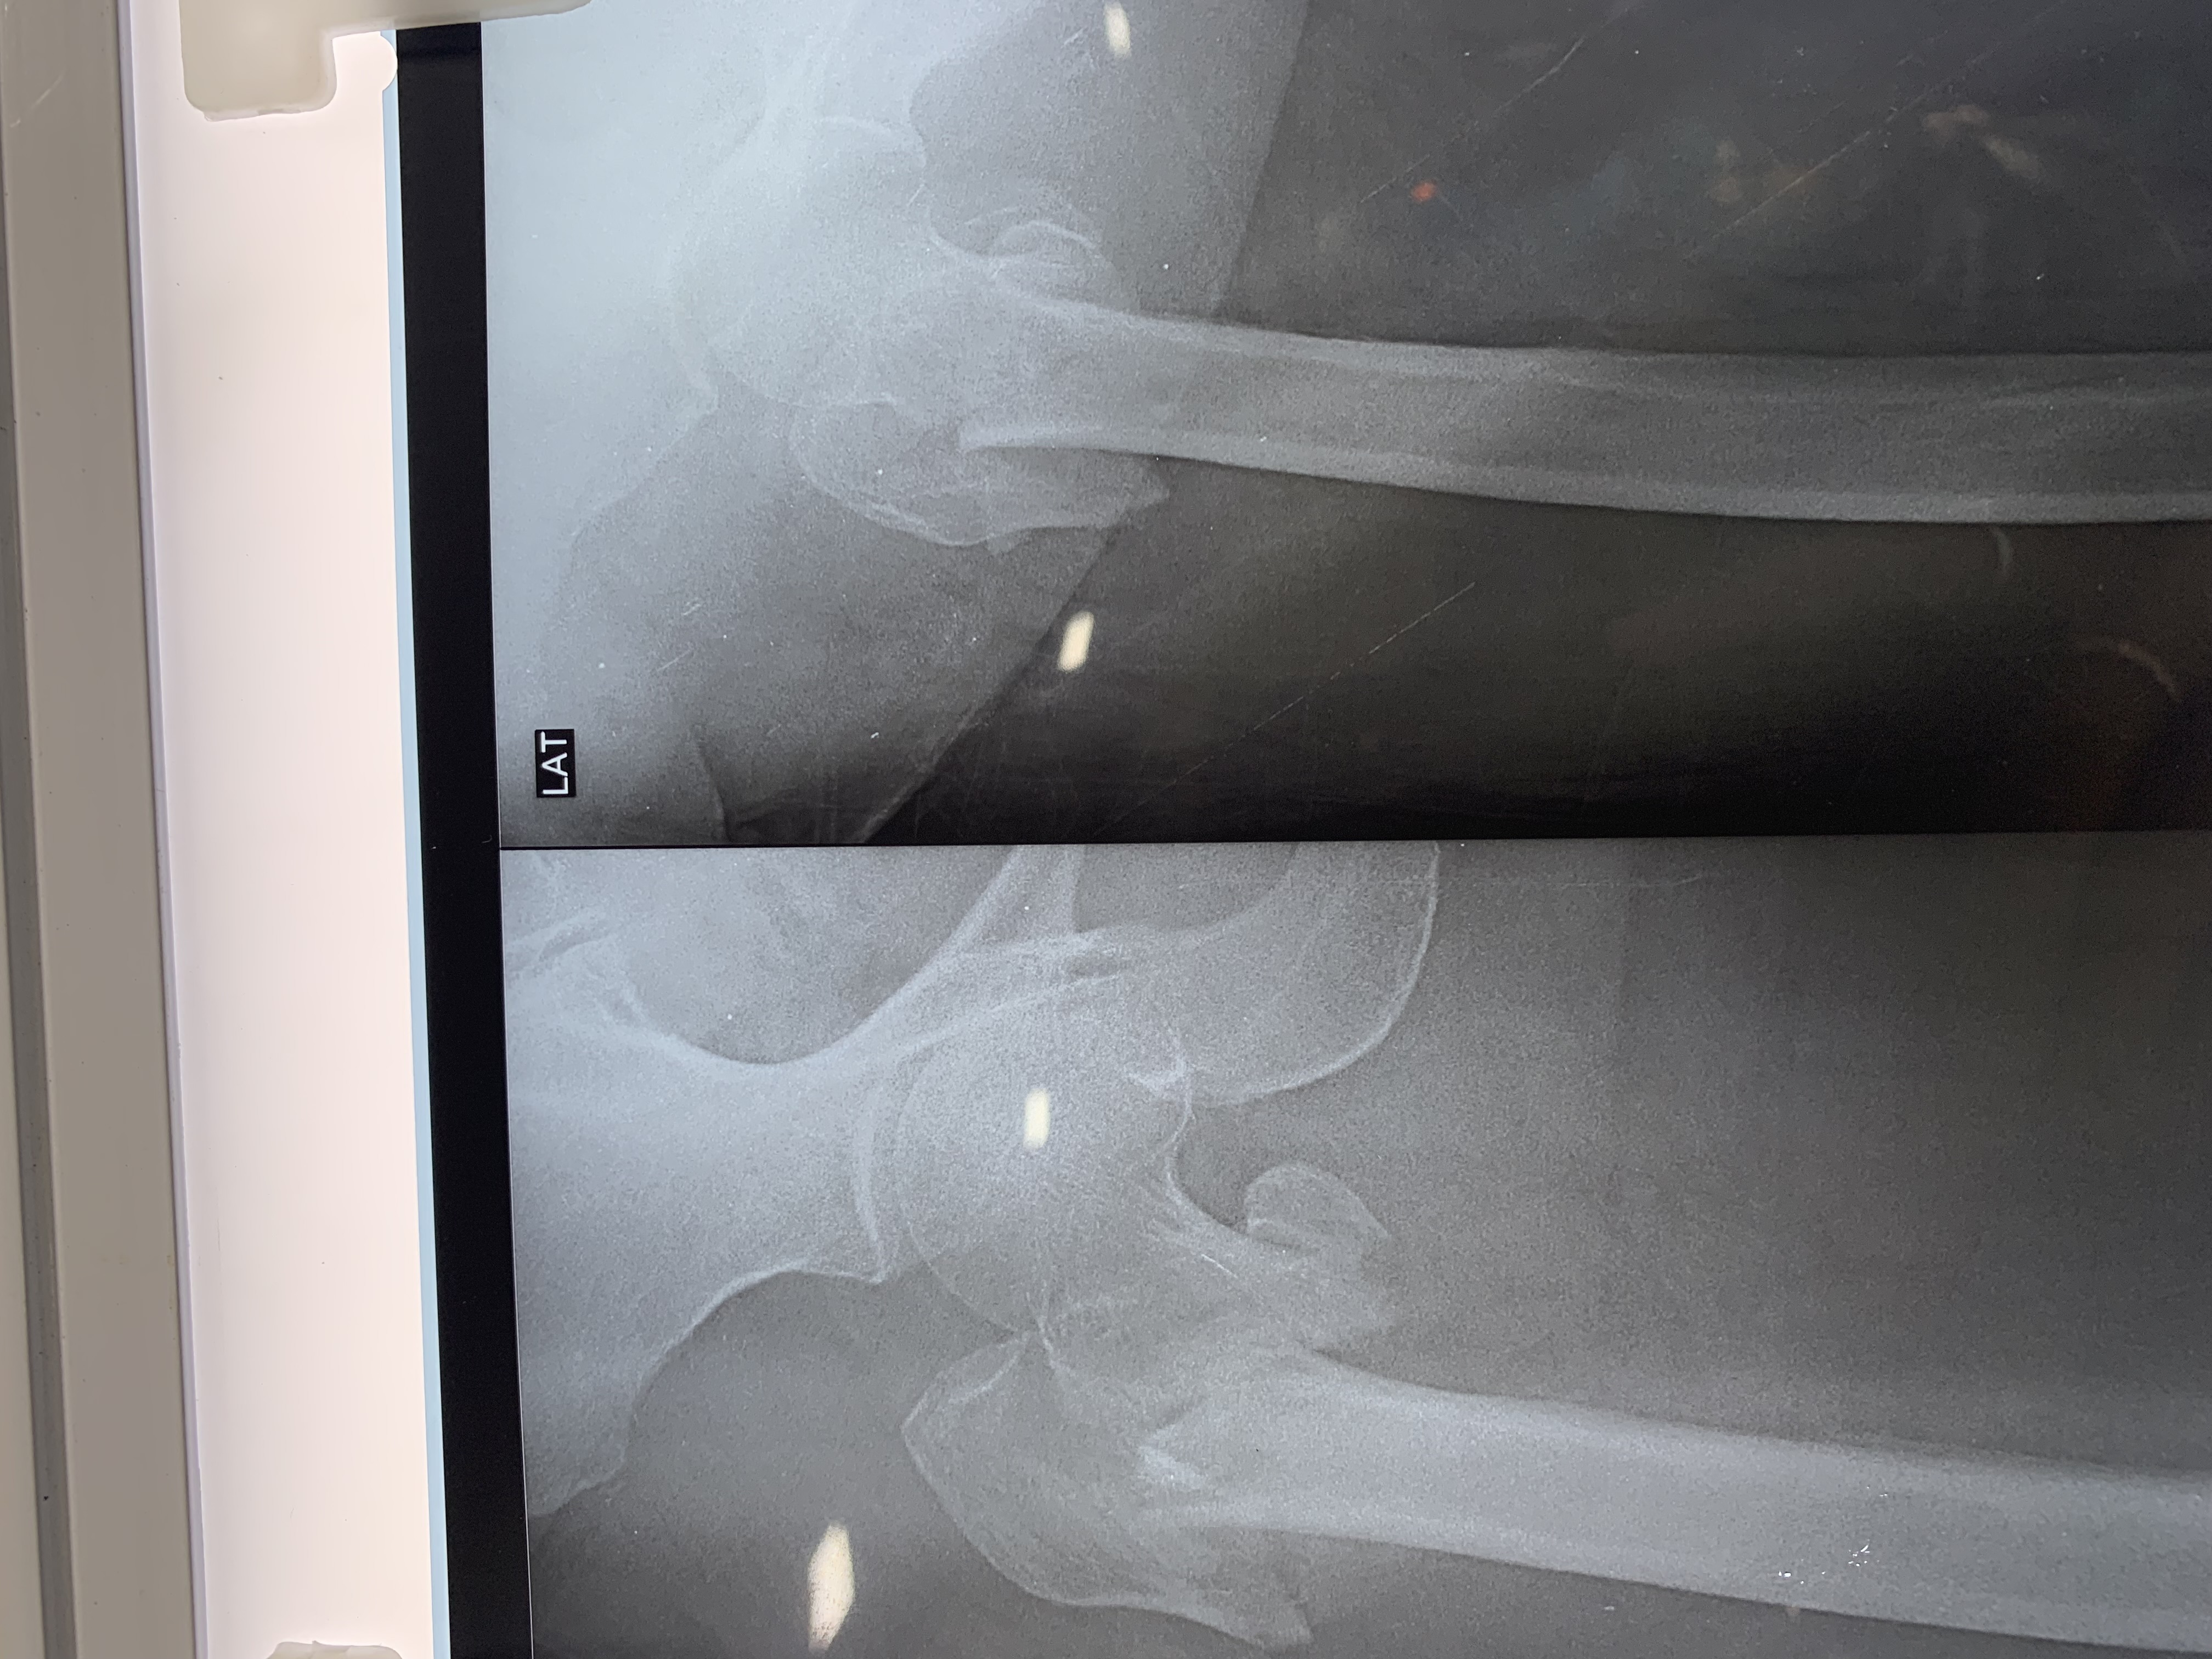

Complex Distal Humerus Comminuted Fracture

Complex Distal Humerus Comminuted Fracture

Complex Distal Humerus Comminuted Fracture

Complex Distal Humerus Comminuted Fracture

Complex Distal Humerus Comminuted Fracture

Complex Distal Humerus Comminuted Fracture

Complex Distal Humerus Comminuted Fracture

Complex Distal Humerus Comminuted Fracture

Complex Distal Humerus Comminuted Fracture

Complex Distal Humerus Comminuted Fracture

Complex Distal Humerus Comminuted Fracture

Complex Distal Humerus Comminuted Fracture

Complex Distal Humerus Comminuted Fracture

Complex Distal Humerus Comminuted Fracture